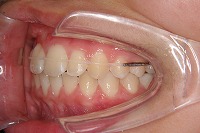

反対咬合を主訴に来院された、右側唇顎裂の10歳6ヵ月の女の子です。診断「右側唇顎口蓋裂で反対咬合を伴う」1期治療で反対咬合の解消と上顎の前歯の並びを修正しました。2期治療は抜歯をせず治療を行いました。